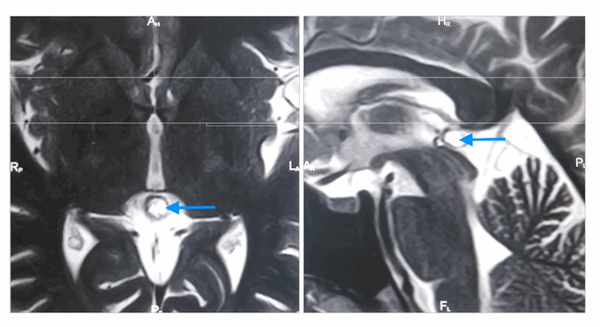

Киста шишковидной железы с типичным гиперинтенсивным сигналом на МРТ (Т2 ВИ) (отмечена синей стрелкой). Слева: аксиальная томограмма, справа - сагиттальная

На МРТ наблюдаются следующие признаки:

- Типичный изо- или гипоинтенсивный сигнал по сравнению с паренхимой головного мозга

- В 55-60% случаев гиперинтенсивный сигнал по сравнению с ликвором

- Сигнал обычно однородный

- Сигнал высокой интенсивности

- Обычно слегка менее интенсивный по сравнению с ликвором

- Сигнал высокой интенсивности, который часто не подавляется полностью

- Рестрикция диффузии отсутствует

- Примерно 60% кист накапливают контраст

- Накопление контраста в большинстве случаев происходит в виде тонкого (меньше 2 мм) и ровного «ободка» (полного или неполного)